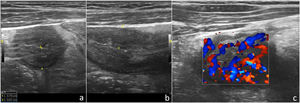

Presentamos el caso de un niño de 9 años de edad, sin antecedentes personales y familiares de interés clínico, que consulta por presentar deposiciones líquidas y molestias abdominales inespecíficas de 2 semanas de evolución. En la exploración física presenta discreto grado de dolor abdominal difuso a la palpación profunda del mismo sin signos de irritación peritoneal. Se realizó una ecografía clínica abdominal que puso de manifiesto un peristaltismo disminuido y un engrosamiento mural del íleon terminal, con estratificación mural aún conservada, sugerente de EC en las fases iniciales de la enfermedad, que se confirmó mediante RM en la unidad de gastroenterología pediátrica (figs. 1 y 2).

Corte longitudinal (a) y transversal (b) con sonda lineal de alta frecuencia (8-12MHz) a nivel de fosa iliaca derecha donde se identifica el íleon terminal con engrosamiento generalizado de su pared y cuantificación de su espesor. c) Imagen similar a la primera donde se evidencia un aumento de la vascularización del íleon mediante Doppler color.